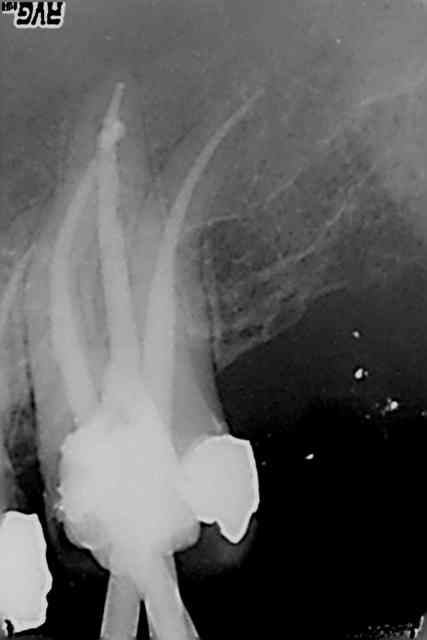

Cas pratique.4eme sur 27. Je me demande quel est le sagouin qui a fait l'endo. Oublié un mv2. Je lui ai taillé un short devant le patient. J'ai eu raison ?

R45 xndtrm - Eugenol

R39 iptohh - Eugenol

Ce praticien c'est moi. Endo faite en 2005. Ptain pas de digue en plus.))))) J'ai expliqué le pourquoi du comment ca a merdé, au patient. J'en ai bien chié pour le trouver ce mv2, meme tordu une sonde droite.

R48 hodugh - Eugenol